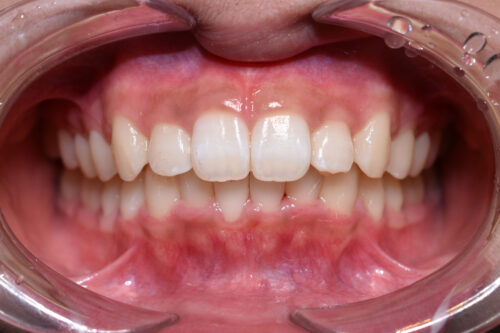

歯のがたつき(叢生)と出っ歯の非抜歯矯正治療)ワイヤー7か月(かみ合わせ変化)

初診時年齢14歳女性

歯のがたつき(叢生)と

出っ歯

を気になさり

巣鴨 ・ 池袋よりひとつ隣駅の東京都豊島区大塚駅すぐの大塚たまみ矯正歯科へ

来院されました。

過蓋咬合: 下の歯が深く噛みこみ

また

ANGLE 2級 : 上顎前突傾向で

出っ歯を呈していました。

本症例も

矯正治療の精密検査後

非抜歯矯正治療計画を立案しました。

ワイヤー矯正治療7か月後です。